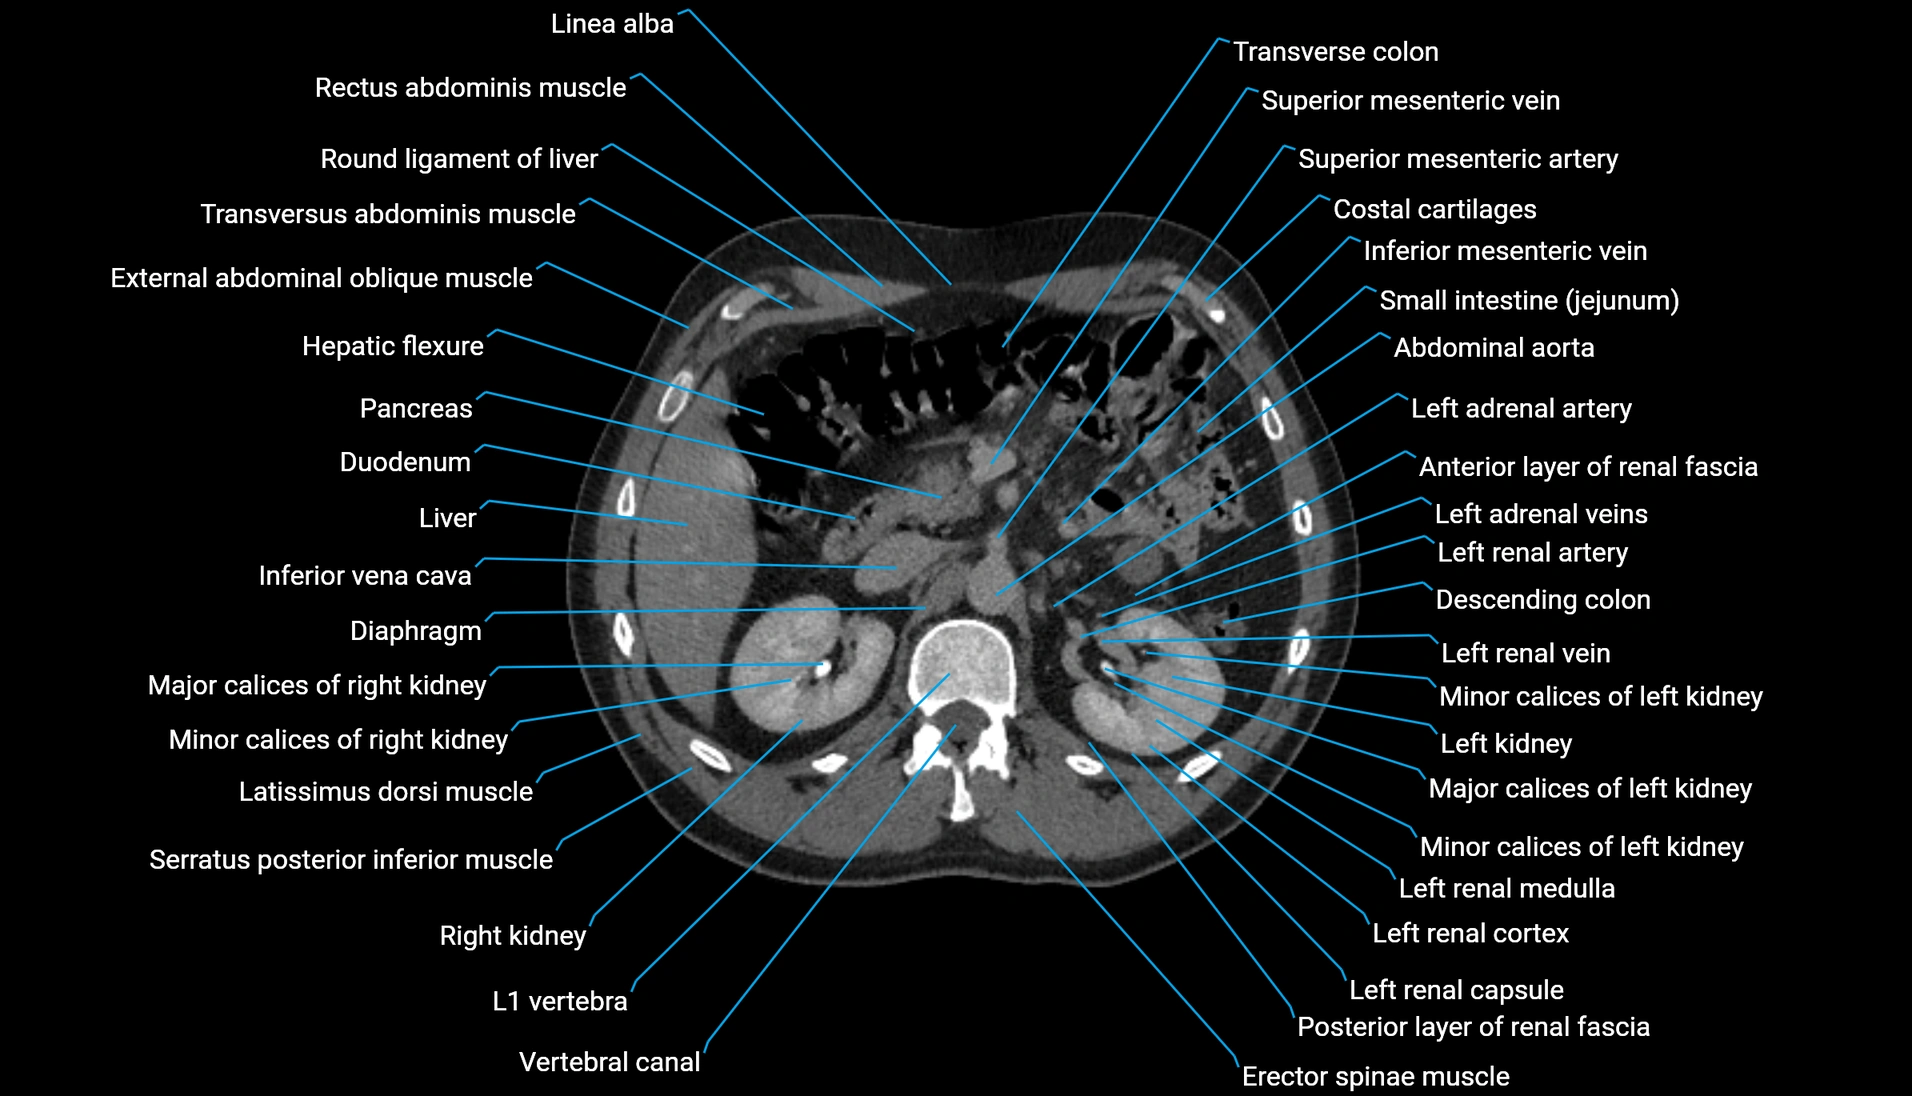

CT Appearance

Non-contrast CT:

-

Demonstrates cortical bone of acetabular rim in excellent detail

Detects fractures, dysplasia, retroversion, or bony overcoverage (pincer impingement)

3D reconstructions used in preoperative hip surgery planning

CT image